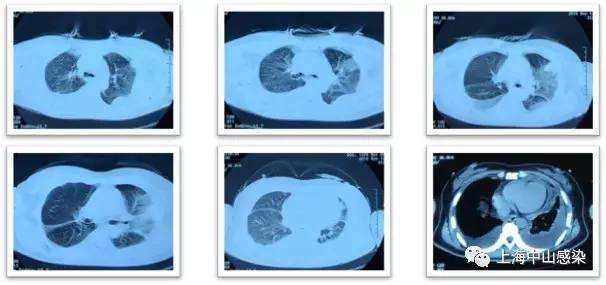

6月14日复查胸部CT2:肺炎稍吸收,但双侧胸腔积液更加明显

肺吸虫血清抗体阳性,诊为肺吸虫病,吡 喹酮1g(200mg*5片),tid,3天,8.29 CT3复查病灶明显吸收。

2.本例有意思的地方是有不符合常见寄生虫病的特点:血嗜酸性粒细胞不高;血IgE正常;胸腔积液无嗜酸性粒细胞;肺内未见虫体移行性空洞或囊性病灶;但也有多处提示:多浆膜腔积液;抗菌治疗无效;肺内病灶呈游走性;患者喜食醉蟹。